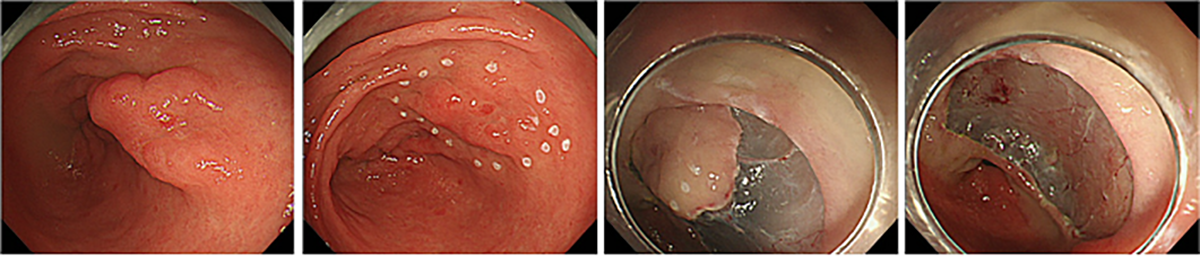

食道や胃の早期がんに対する内視鏡治療は、がんが発生した消化管の表層のみを切除する治療法です。現在主に行われている内視鏡治療が、内視鏡的粘膜下層剥離術(ESD)です。

ESDでは、比較的大きな病変でも内視鏡的に切除することが可能です。ESDを行う際には、まず電気メスを用いて病変の周囲に目印を付けます(図)。次に、粘膜下層(病変の裏側)に薬液を注入して病変を浮かせた後、目印を含めて病変の周囲を電気メスで切開します。その後、粘膜下層を切り進めながら病変を切除していきます。切除した病変は回収し、病理検査を行います。病理検査の結果によっては、外科手術などの追加治療を検討する場合があります。